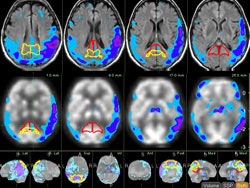

MIMneuro is designed for nuclear medicine studies of Alzheimer's disease and frontal dementia, according to the company. The software performs registration and fusion of brain areas, and compares them to a database of normal studies, with regions either showing increased or decreased metabolic activity depending on the pathology. Region-based or voxel-based comparisons are possible, the company said.

The software also conducts structure-based reconstruction rather than intensity-based reconstruction. MIMneuro can be purchased separately on a standalone basis or used as an add-on module to the company's flagship MIMfusion software.

| MIMneuro lets users fuse brain images from multiple modalities. |